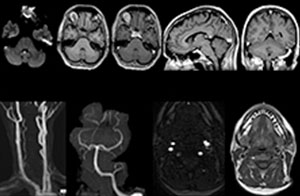

cervical spine mri in ed

Cervical spine routine exam

This patient presented with headache that was worse with neck flexion and we see a Chiari 1 malformation with low-lying cerebellar tonsils as well as some degenerative cervical thrombolytic change.